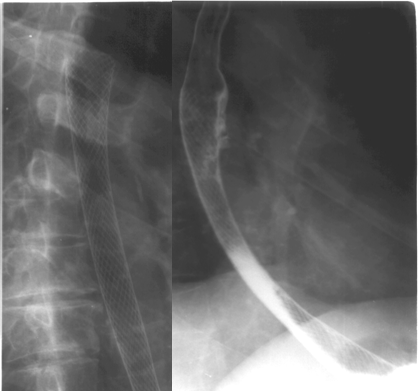

Figure 4. Malignant esophageal stenosis bridged with a metallic expandable stent (Ultraflex®- Boston Scientific)